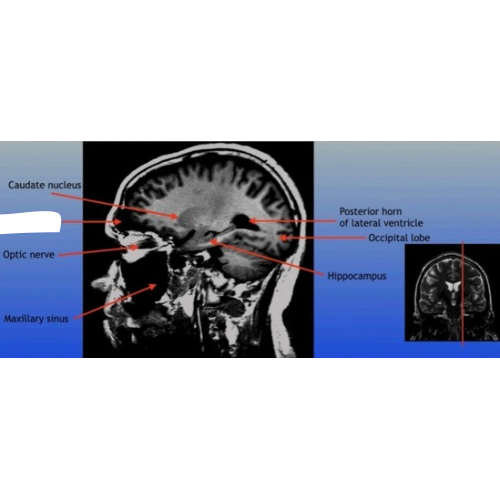

Caudate Nucleus

A C-shaped structure within the brain's basal ganglia, involved in various functions including motor control and learning.

Optic Nerve

The bundle of nerve fibers that transmits visual information from the retina to the brain. It plays a crucial role in the sense of sight.

Maxillary Sinus

A paired cavity located within the maxilla, situated below the eyes, that contributes to sinus drainage and helps lighten the weight of the skull.

Posterior Horn of Lateral Ventricle

The posterior part of the lateral ventricle, involved in the production and circulation of cerebrospinal fluid within the brain.

Hippocampus

A critical region in the brain associated with memory formation and spatial navigation, located in the medial temporal lobe.